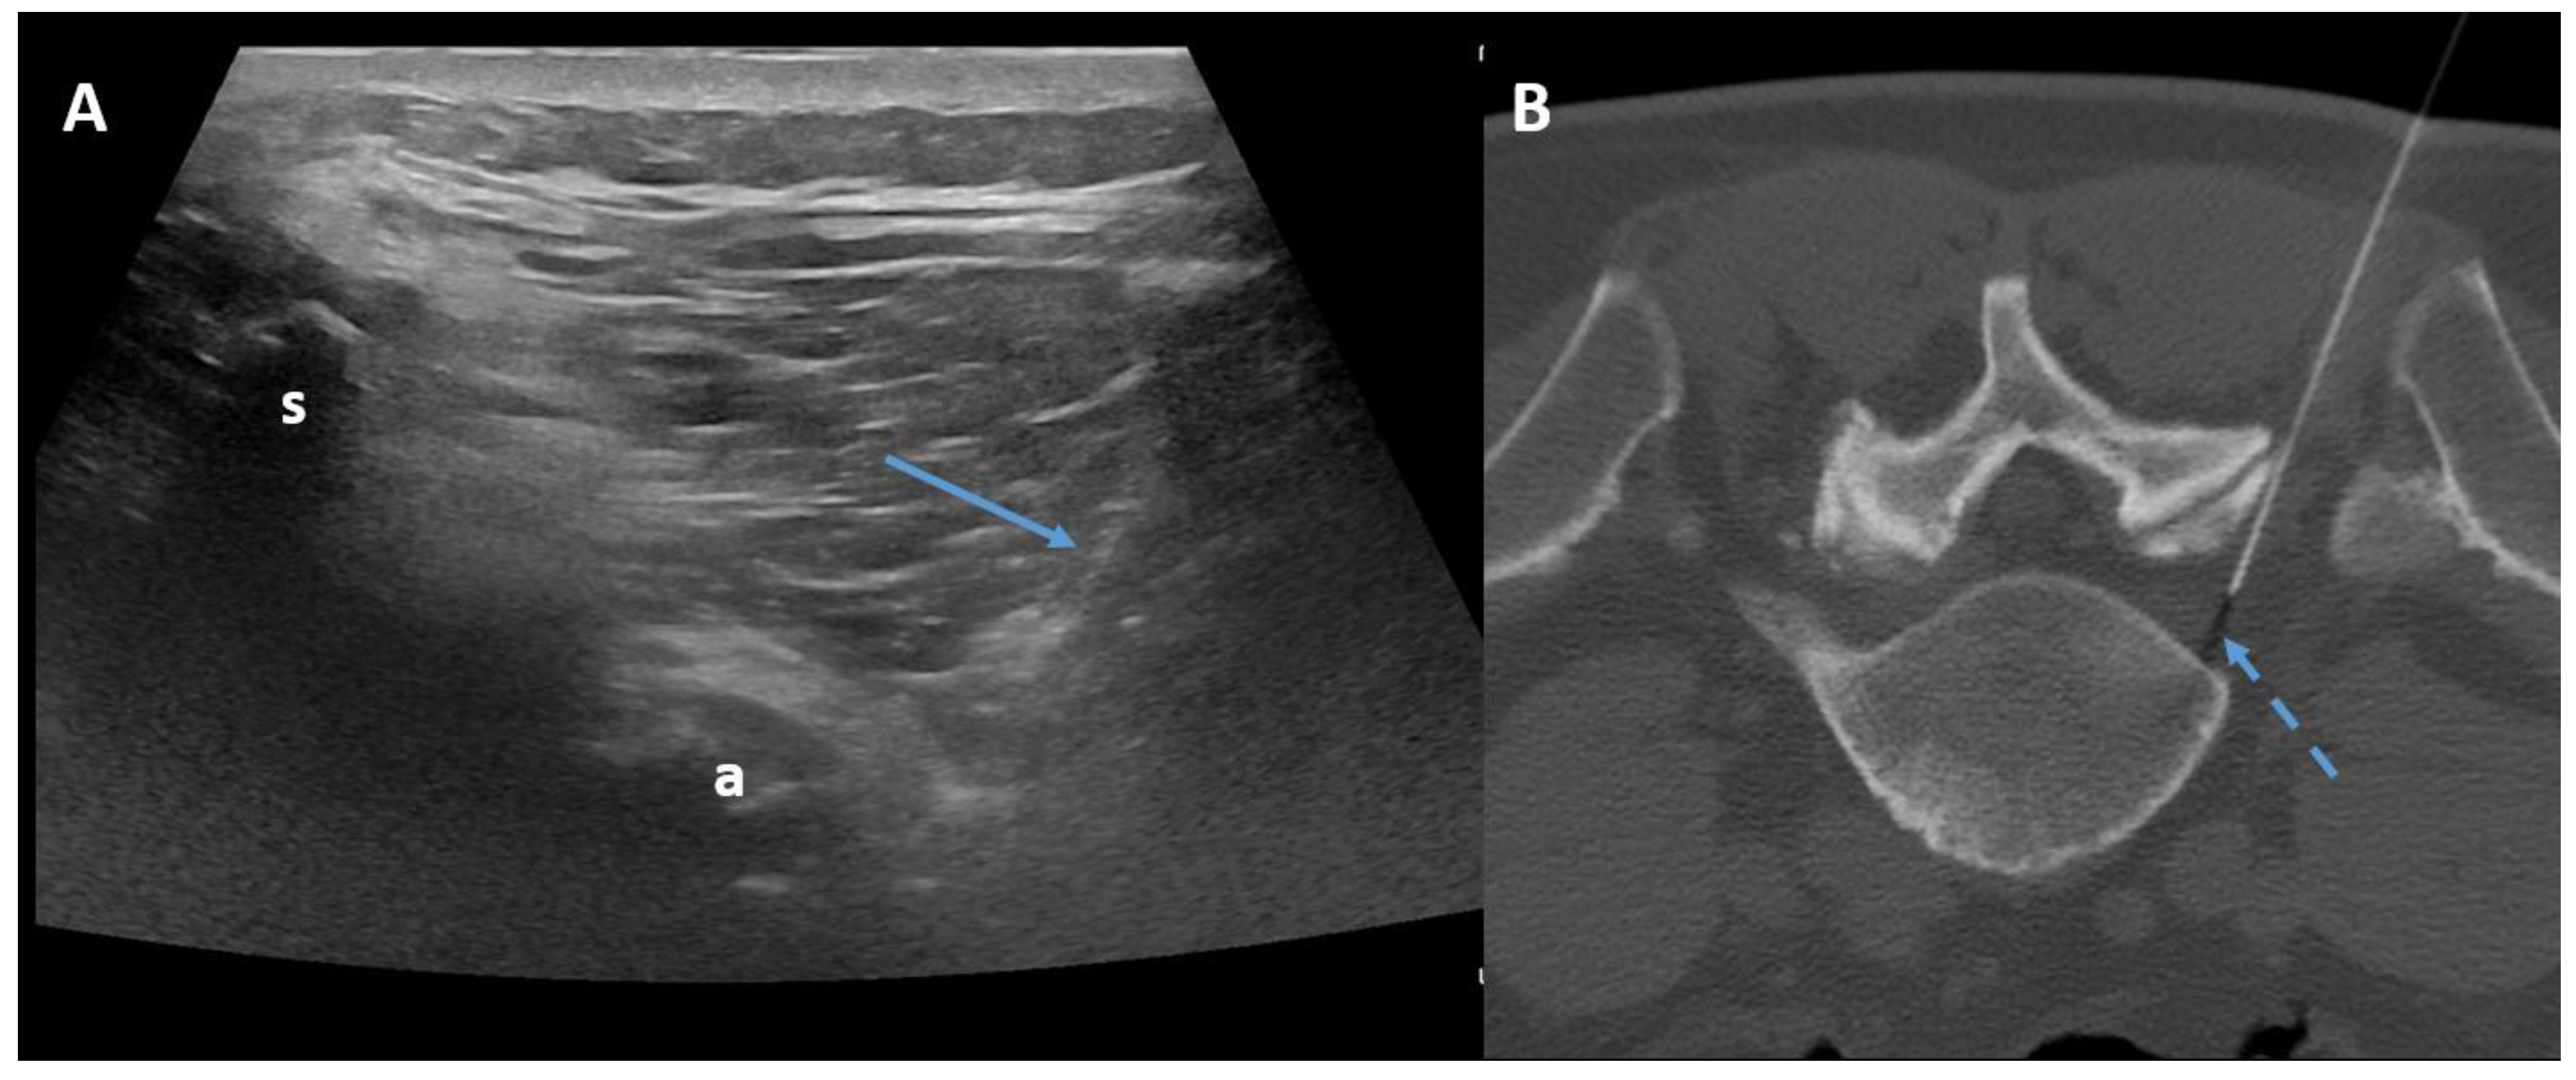

- Latini, E.; Curci, E.; Nusca, S.; Lacopo, A.; Musa, F.; Santoboni, F.; Trischitta, D.; Vetrano, M.; Vulpiani, M. Medical Ozone Therapy in Facet Joint Syndrome: An Overview of Sonoanatomy, Ultrasound-Guided Injection Techniques and Potential Mechanism of Action. Med. Gas Res. 2021, 11, 145. [Google Scholar] [CrossRef] [PubMed]